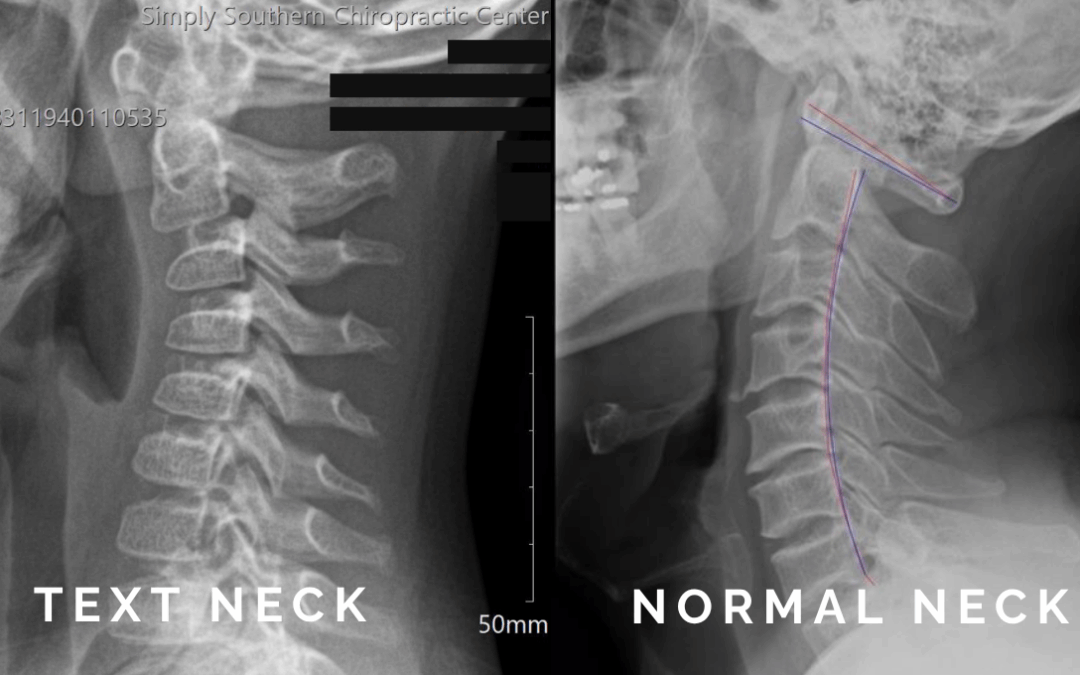

Tech Neck and Text Thumb: How Chiropractic Care Helps Patients of All Ages

Key Points Tech neck is neck and shoulder strain caused by spending too much time looking down at phones, tablets, or computers. Text thumb is pain and stiffness in the thumb or wrist from repetitive scrolling, texting, and gaming. Kids and teens are most at risk...